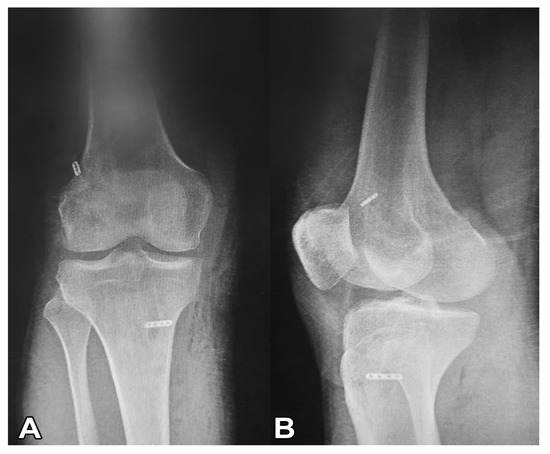

2.2. Surgical Treatment (Modified All-Inside Technique)